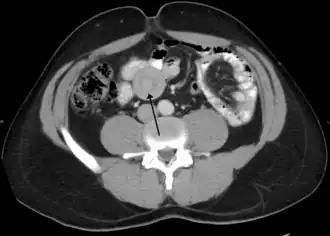

Инвагина́ция кише́чника  — выделяемый в отдельную нозоформу вид непроходимости кишечника, причиной которого является внедрение одной части кишечника в просвет другой[3].

В зависимости от локализации различают виды кишечной инвагинации:

1. тонко-тонкокишечная

2. тонко-толстокишечная

3. тонко-слепокишечная (илеоцекальная)

4. толсто-толстокишечная

5. тонко-толсто-слепокишечная

Наиболее часто наблюдается инвагинация в области илеоцекального угла (более 95 %).